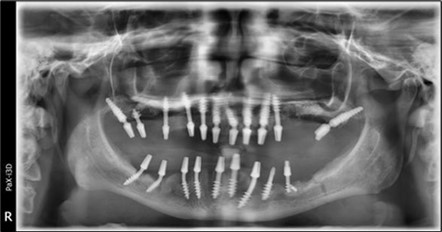

June 2022: Patient presented to our clinic for immediate-loading implant treatment At the time of presentation in 06. 2022, radiologically, advanced peri- implantitis is observed around the implants, with loss of native bone in the affected distal areas (Figure 1)

Figure 1.Panoramic overview picture before rehabilitation 06.2022

Panoramic overview picture before rehabilitation 06.2022